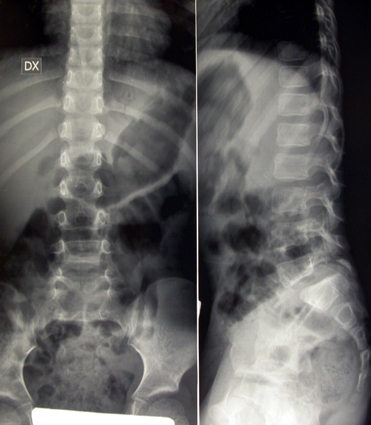

Per spondilolisi si intende l’interruzione di quella parte dell’arco posteriore vertebrale compresa fra le due apofisi articolari (fig 1). Se bilaterale, essa può favorire lo scivolamento in avanti di una vertebra rispetto a quella sottostante, realizzando così la spondilolistesi (fig 2).

La spondilolisi non comporta necessariamente l’instaurarsi della listesi (= scivolamento, fig 4-5), che si verifica in circa il 50% dei casi, soprattutto in occasione del rapido accrescimento pubertario. I disturbi, se presenti, consistono in lombalgie, scatenate o esacerbate da intense sollecitazioni funzionali e alleviate dal riposo, a volte accompagnate da irradiazioni cruralgiche o sciatalgiche. Quando lo scivolamento vertebrale è cospicuo, può coesistere una certa retrazione dei flessori posteriori delle cosce, che limita la flessione delle anche sul bacino e l’estensione delle ginocchia ad anche flesse (pseudo-Lasègue), oltre a contribuire ad accentuare la lordosi lombare. Solo di rado nell’età evolutiva si riscontrano i segni di compressione o di stiramento delle radici del midollo (parestesie, iporeflessie, deficit muscolari). La scoperta, spesso casuale, di una spondilolistesi asintomatica non obbliga necessariamente alla completa inattività sportiva, che potrà essere concessa in forma non agonistica, evitando le discipline più traumatizzanti per il rachide, cui si è accennato in precedenza. La regolare osservazione clinico-radiografica di questi soggetti, specialmente nella fase di massima crescita, permetterà di verificare l’evolutività delle scivolamento e di prendere gli opportuni provvedimenti. La comparsa della sintomatologia rappresenta l’indicazione ad iniziare un trattamento ortopedico conservativo (corsetti) o, nei casi più gravi di spondilolistesi, chirurgico (artrodesi vertebrale).